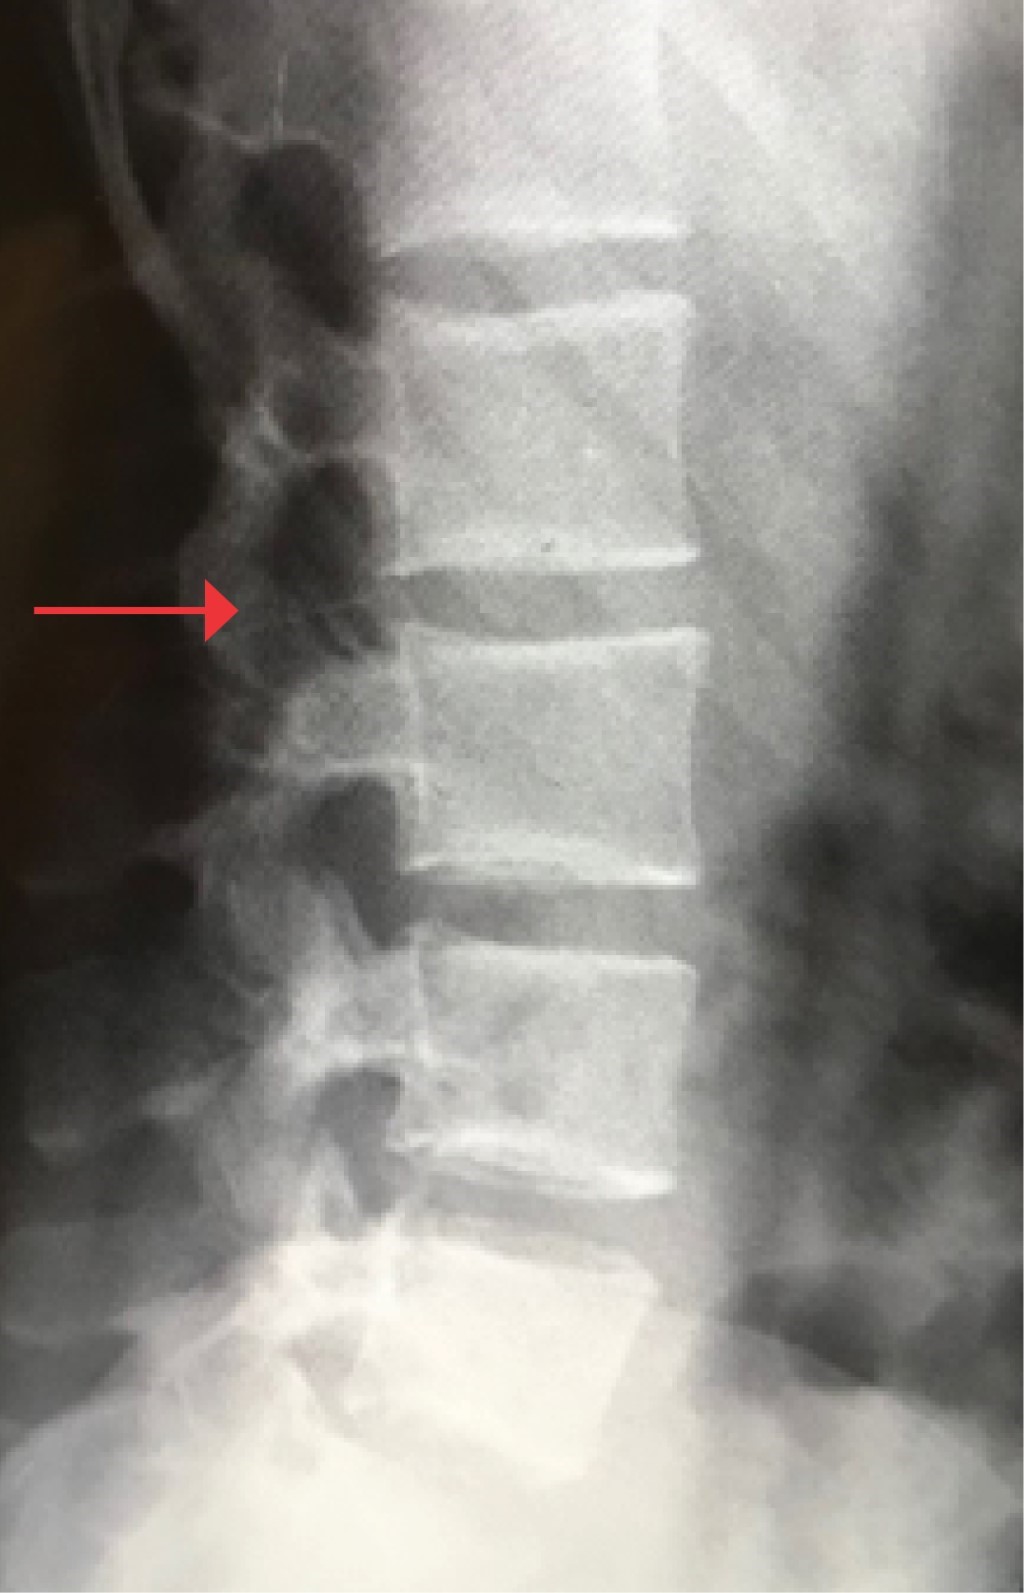

La anestesióloga informó de inmediato a la paciente sobre el incidente que había ocurrido y marcó el área de inserción. En ese momento, la mujer no presentaba ninguno de los síntomas asociados con el fragmento de la aguja que había quedado dentro de su columna, así que se determinó no realizar un examen neurológico, ya que su diagnóstico requería practicarle la cesárea de forma urgente, y así evitar mayores complicaciones del binomio. La anestesióloga y la ginecóloga decidieron continuar con la cirugía, pero cambiaron el procedimiento inicial por la aplicación de anestesia general balanceada, iniciado con tratamiento antiinflamatorio no esteroideo (AINEs), metamizol 2 g en infusión, así como la administración de esteroide, dexametasona 8 mg intravenoso. Por su parte, la paciente se mostró de acuerdo con las especialistas, así que se llevó a cabo la intervención quirúrgica de cesárea y, posteriormente, se le tomó una radiografía de columna anteroposterior y lateral (Figuras 2 y 3). Debido a que el hospital donde se presentó el evento no cuenta con esos recursos, no se realizó otro tipo de estudio como la tomografía axial computarizada y la resonancia magnética. En cuanto se obtuvieron los resultados de las radiografías, se solicitó interconsulta con un médico neurocirujano, quien refirió que tenía que ser intervenida de nueva cuenta. La cirugía se programó y se efectuó de inmediato.

Figura 3